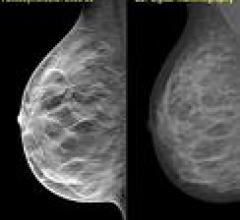

The women’s health channel includes news, videos, podcasts and other content related to technology used to detect and treat breast cancer and cervical cancer, including mammography, breast magnetic resonance imaging (MRI), automated breast ultrasound (ABUS), breast ultrasound, breast biopsy and breast radiation therapy.

Despite decades of progress in breast imaging, one challenge continues to test even the most skilled radiologists ...